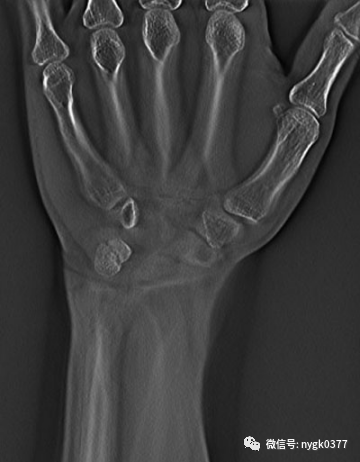

断层融合功能应用在隐蔽性骨折的确诊:

岛津有哪些影像设备岛津 C200拥有性能完善的影像链系统_https://www.jmylbn.com_新闻资讯_第10张

豆状骨骨折